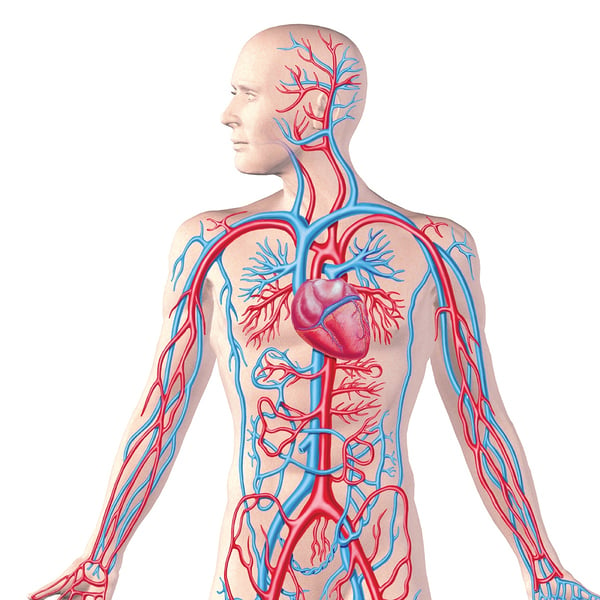

Кровеносная система человека: структура и функции

Раздел: Идеи и советы